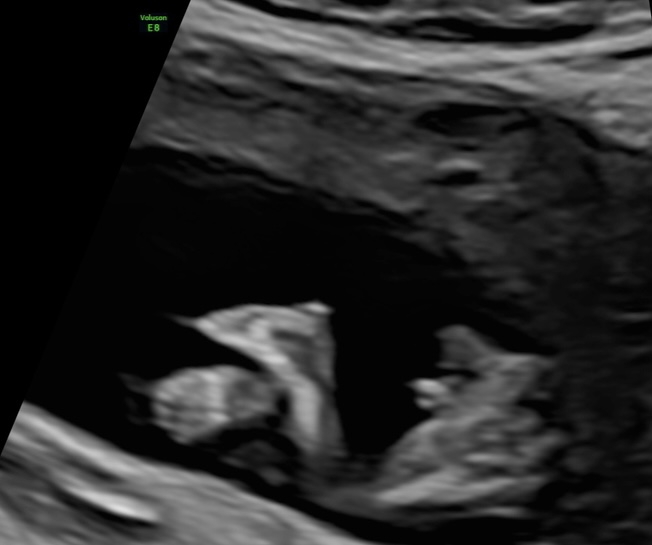

ich bin derzeit in der 13. SSW und hatte letzte Woche einen Ultraschall. Was meint ihr, kann man das Geschlecht erkennen? Der Arzt hatte eine klare Tendenz die er uns leider bisher nicht mitgeteilt hat. Ich kann leider nichts wirklich erkennen. Hier die Bilder aus 12+3. Vielen Dank fürs Miträtseln :)ip8o4cqlye7n.jpeg